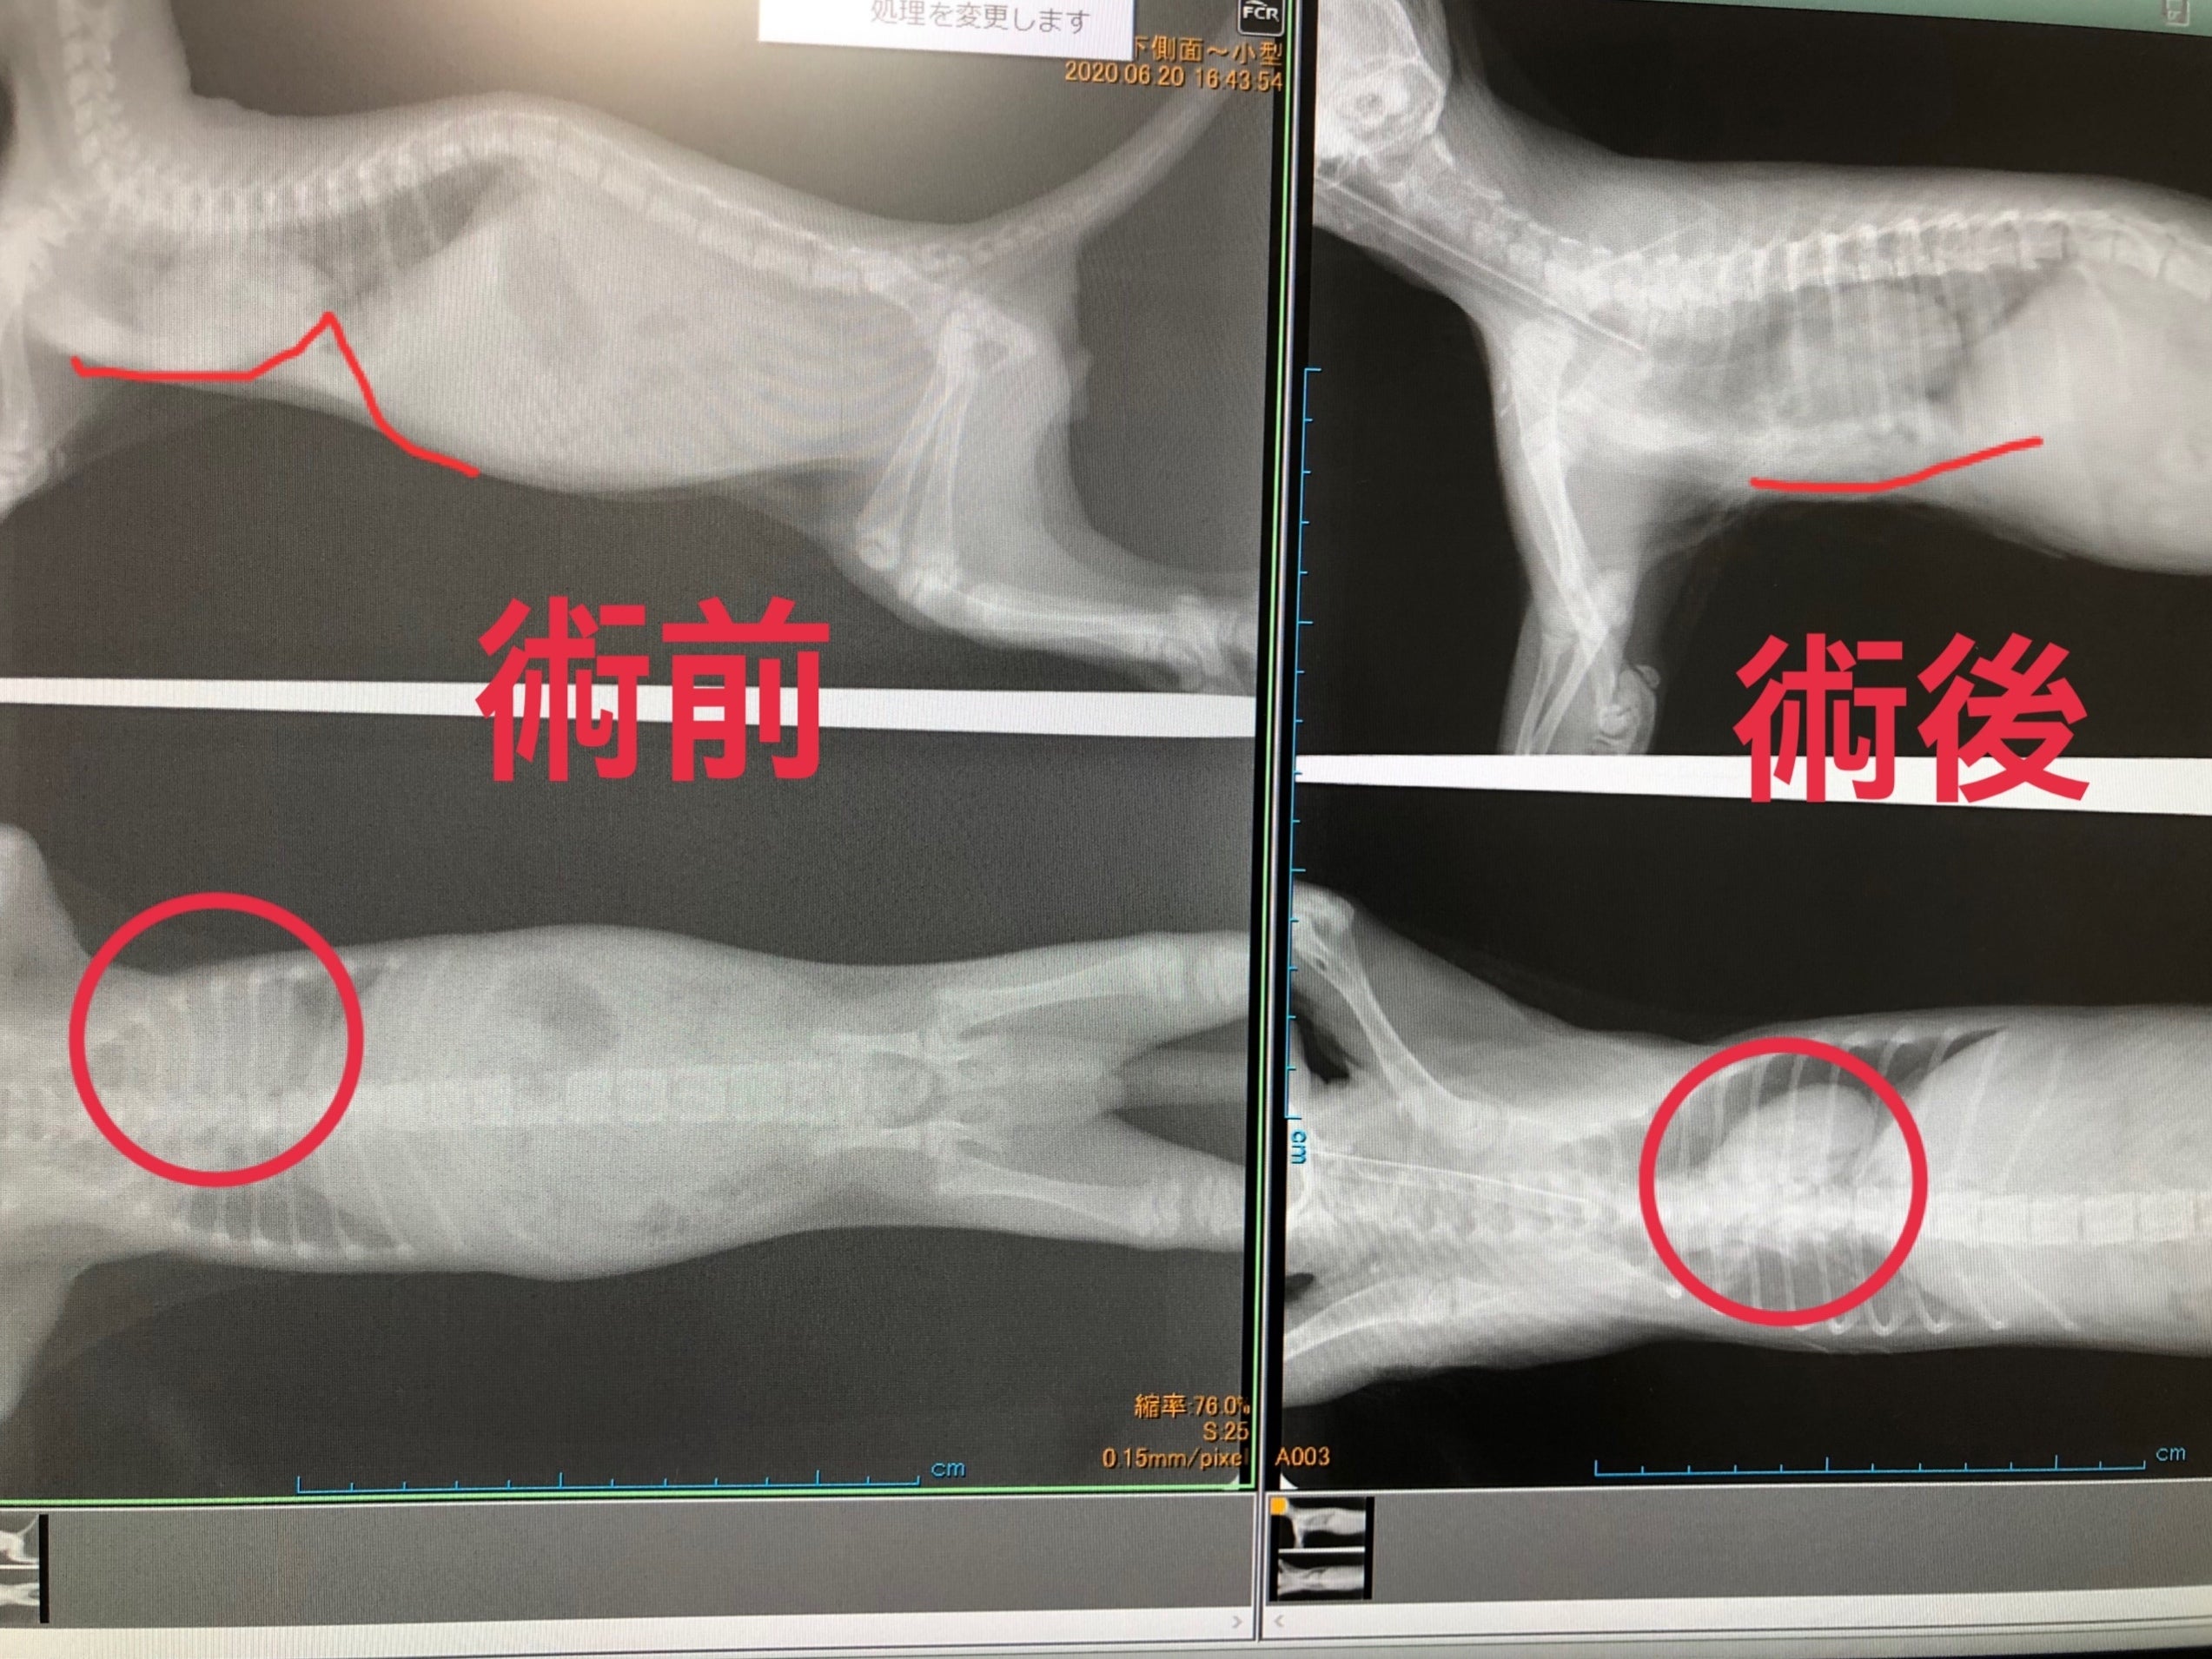

これがコロ助ちゃんの手術前と手術後のレントゲン写真です。

鋭角に食い込んでいた骨がほぼ平らになり、骨に阻害されていた心臓も本来の位置に近くなっています。

遊んでいても少し走るとすぐに口の中もお腹も紫色になりチアノーゼを起こしていたコロ助ちゃんですが、1ヶ月の安静という試練はあれどきっと元気になってくれると思います。